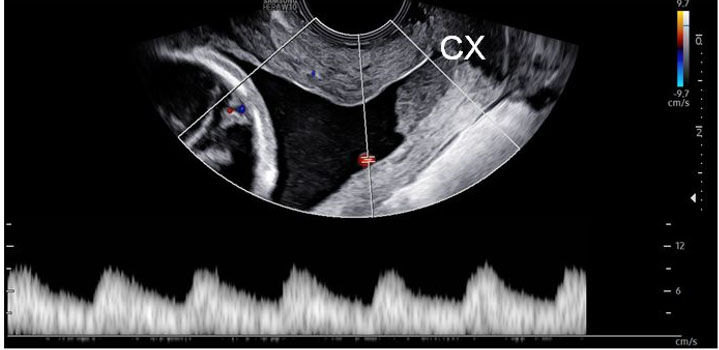

At 21w2d, CL was 1 cm with funneling and sludge. Cervical cerclage was discussed as a surgical management option given continued cervical shortening despite compliance with progesterone. The unique risks posed by vasa previa were discussed such as further cervical shortening increasing the risks of both pregnancy loss and fetal hemorrhage, although cerclage placement posed its own risks given fetal vessels in the cervical canal. The patient consented to the procedure and McDonald cerclage was placed successfully. Color Doppler ultrasonography was utilized to map fetal vessel location prior to surgery to reduce the risk of fetal hemorrhage during cerclage placement and to allow for maximum gain in CL (Figure 3).

Figure 3: PW Doppler examination for fetal vessel mapping— Transvaginal sonogram with PW Doppler examination to locate and map fetal vessels prior to placement of cerclage. PW Doppler showing fetal arterial waveform. PW, pulse wave; CX, cervix.